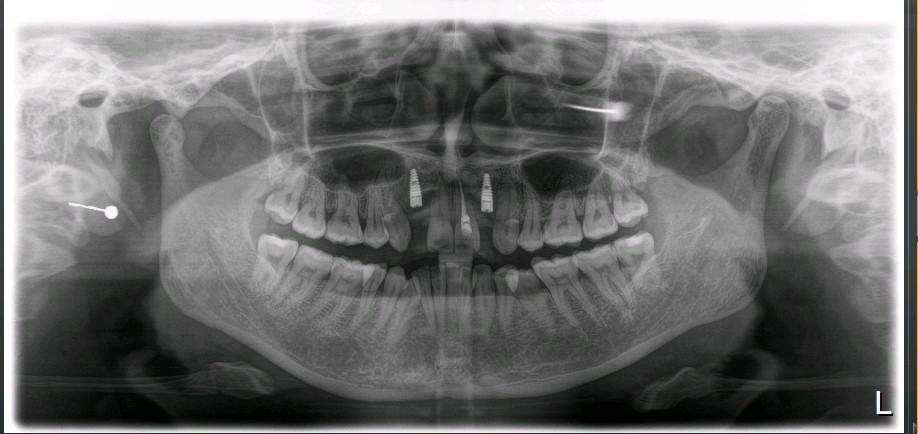

术后